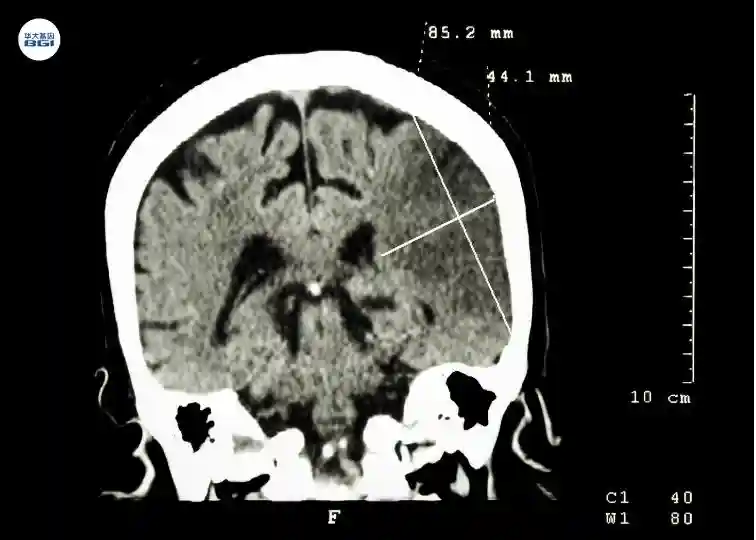

脑部CT,显示病人左半球脑梗塞(缺血性中风)